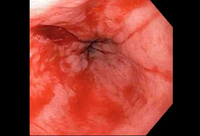

Mallory-Weiss tear

Mallory Weiss tear after application of through-the-scope clip results in hemostasis

From the personal collection of Douglas Adler; used with permission